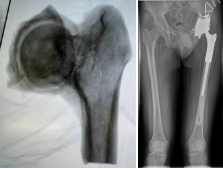

骨肉瘤是最常见的原发性恶性骨肿瘤,好发于10-25岁青少年。骨肉瘤增殖能力强、进展迅速、易发生早期转移,患者的预后较差。考虑到患者年轻,切除肿瘤的同时如何保证患肢的功能成为了问题的关键。诊断明确后,科室专家在胡勇主任医师的带领下为患者定制了新辅助化疗为保障的保肢治疗方案。化疗后达到了安全的外科边界,3D打印手术模型,精准切除肿瘤,定制截骨导板和3D打印的髋臼为患者量身定制3D打印全髋关节假体。

胡勇主任医师、徐生林副主任医师成功为患者实行了肿瘤全关节广泛切除3D打印定制髋关节假体置换术。该手术方案需要医工结合,技术难度高,但可将肿瘤切除彻底,肢体达到功能重建。